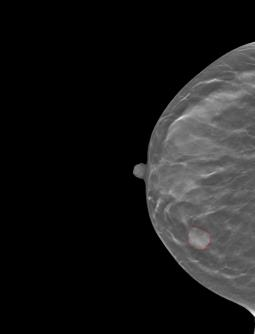

Accurately classifying malignancy of lesions detected in a screening scan plays a critical role in reducing false positives. Through extracting and analyzing a large numbers of quantitative image features, radiomics holds great potential to differentiate the malignant tumors from benign ones. Since not all radiomic features contribute to an effective classifying model, selecting an optimal feature subset is critical. This work proposes a new multi-objective based feature selection (MO-FS) algorithm that considers both sensitivity and specificity simultaneously as the objective functions during the feature selection. In MO-FS, we developed a modified entropy based termination criterion (METC) to stop the algorithm automatically rather than relying on a preset number of generations. We also designed a solution selection methodology for multi-objective learning using the evidential reasoning approach (SMOLER) to automatically select the optimal solution from the Pareto-optimal set. Furthermore, an adaptive mutation operation was developed to generate the mutation probability in MO-FS automatically. The MO-FS was evaluated for classifying lung nodule malignancy in low-dose CT and breast lesion malignancy in digital breast tomosynthesis. Compared with other commonly used feature selection methods, the experimental results for both lung nodule and breast lesion malignancy classification demonstrated that the feature set by selected MO-FS achieved better classification performance.